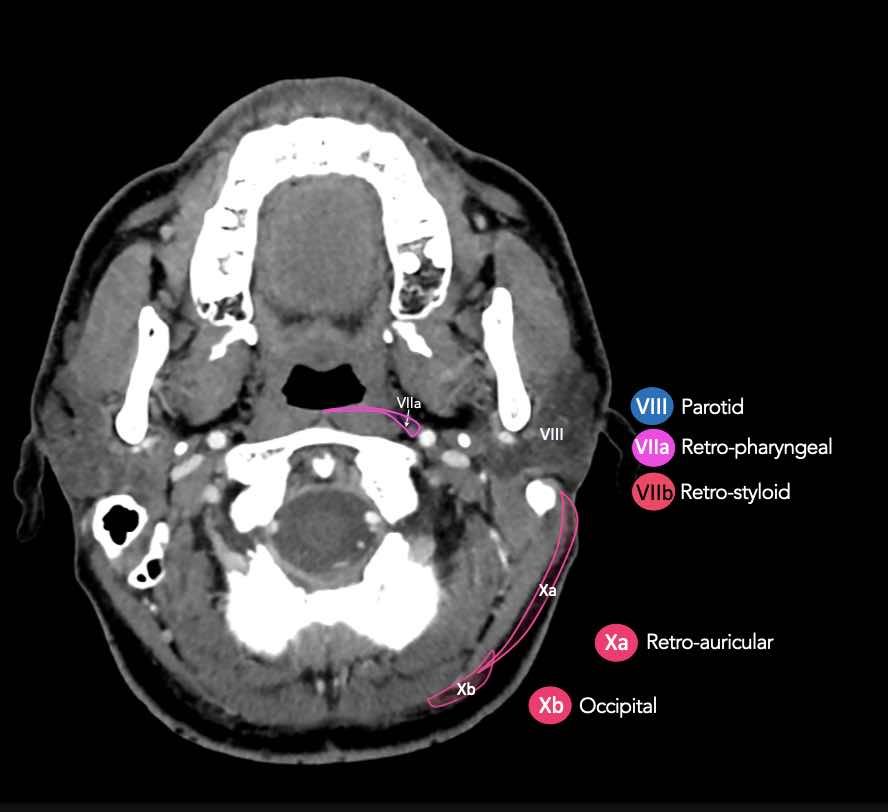

CT Scan Mặt Cắt Ngang (Axial CT)

Các lát cắt CT mặt phẳng ngang tương ứng với hình minh họa tổng quan.

Các lát cắt CT mặt phẳng ngang với hình ảnh chi tiết hơn.

Nhấp vào hình ảnh để phóng to.